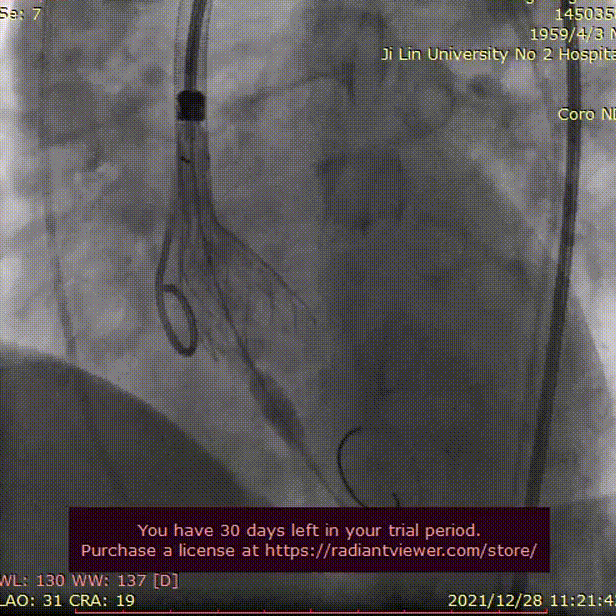

术中影像

主动脉根部造影

20mm球囊充分扩张

瓣膜初始定位

瓣膜逐步释放至工作位

TaurusOne AV26mm瓣膜

瓣下2mm 工作位造影

瓣膜形态良好 位置理想

无瓣周漏